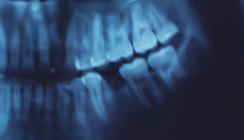

Die Illustration zeigt, wie das Protein Del-1 sowohl die Neutrophilen-Bewegung als auch die Aktivität der Osteoklasten hemmt, um Knochenverlust bei Parodontitis zu verhindern. © University of Pennsylvania, George Hajishengallis